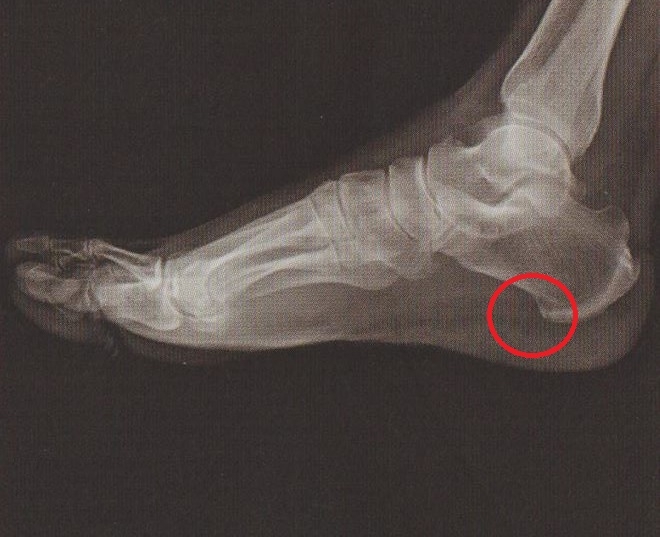

‘족저근막염(발바닥 근막염)’은 종아리 근육의 긴장, 발 아치 구조의 이상, 장시간 보행이나 달리기와 같은 반복적인 사용, 골극 등의 영향으로 인해 발바닥에 위치한 족저근막에 염증이 생기는 질환입니다. 족저근막염002

족저근막염의 통증은 주로 발 뒤꿈치 부근에서 가장 많이 나타나며, 경우에 따라 주변 부위까지 퍼지는 양상을 보이기도 합니다.